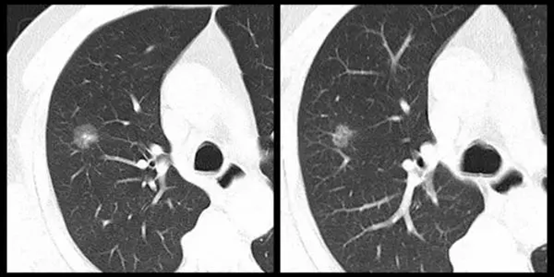

部分患友们知道,找我看肺结节的话,我首先会建议大家先查个薄层胸部CT,为什么呢?我们平时查的胸部CT的每个层面的厚度一般是1mm,甚至是0.5mm,扫完一个人的胸部一般需要300到500个层面。而我们就诊时所携带的外院胸部CT胶片仅仅只有20张到50张图片,层厚非常大,很多结节,特别是小结节压根找不到,看不到!因为有些肺结节本身就几个毫米,可能就漏掉了!这个时候必须看到原版的(医生电脑显示的)胸部CT图片,才能看清肺结节的形态、大小、位置等信息,才能给出合理化的建议。除非部分患者通过云电子图片、带光盘等途径有原版的胸部CT图片,否则,都需要重新再查薄层胸部CT。另外,由于我们医院是心肺部疾病的专科医院,有专门针对肺结节的超薄层胸部CT检查,并且可以进行三维重建、智能辅助分析肺结节的性质,对肺结节的临床判断会更准确。所谓工欲善其事,必先利其器!

通俗的讲啊,一般就是较大的、较浓的、较圆的、周围有毛刺的!这一类的肺结节一般可能有危险,或者说恶性的可能较大。因为从专业角度讲恶性肺结节,有如下特征如:是不消失的磨玻璃影、结节内有不规则血管影、结节边有毛刺、结节外缘有胸膜牵拉征、结节形态是类圆形的,结节有分叶特征等等,有这些特点就要小心是恶性结节。特别是有些肺结节中间是高密度的实性成分,周围有淡淡的磨玻璃影,我们专业叫混合磨玻璃结节,此类结节大概率可能是恶性结节,尤其要小心了!要去靠谱的医院胸外科找专业的胸外科医生看看了,看看是否需要手术切除了!